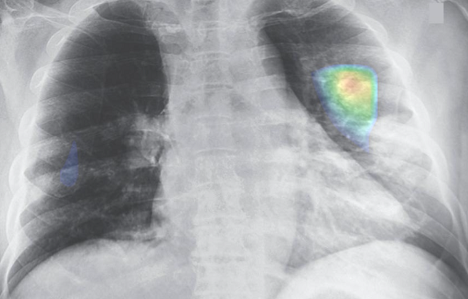

Sản phẩm DrAid for Radiology của VinBrain (thuộc Tập đoàn Vingroup) đã đạt giải ACM SIGAI 2021 ở hạng mục sản phẩm ứng dụng trí tuệ nhân tạo (AI) xuất sắc.

Nhờ ứng dụng trí tuệ nhân tạo AI, các cơ sở y tế có thể đưa ra chẩn đoán chính xác, nâng cao chất lượng dịch vụ khám chữa bệnh.